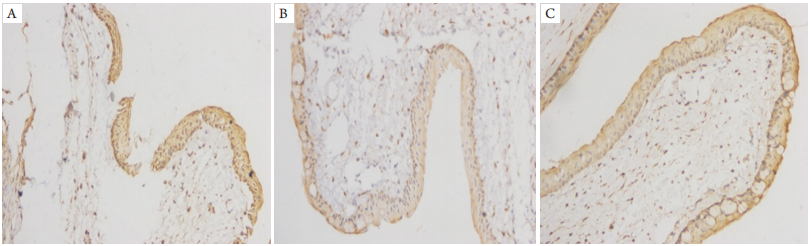

术后第 5 周将大鼠空气栓塞处死进行免疫组织化学检测,结膜上皮细胞 Bax 和 Bcl-2 基因蛋白表达的细胞数情况见图 4, 图 5 。正常组(301.1±132.3)结膜上皮细胞 Bax 蛋白阳性表达的细胞数较对照组(499.3±212.5)和实验组(378.4±153.3)少,且正常组与对照组表达细胞数比较差异有统计学意义(P < 0.05,图 6),与实验组比较差异无统计学意义(P > 0.05);正常组可见大量 Bcl-2 蛋白阳性表达(354.8±104.6),且多于实验组(303.4±143.7),差异无统计学意义(P > 0.05),多于对照组(206.1±101.3),差异有统计学意义(P < 0.05,图 7),呈棕黄色颗粒主要表达在细胞质。对照组结膜上皮细胞中见大量 Bax 蛋白阳性表达于细胞质,呈棕黄色颗粒,实验组中 Bax 蛋白表达相对于对照组明显较少(图 4),两者差异有统计学意义(P < 0.05);实验组结膜上皮细胞中可见大量 Bcl-2 蛋白表达,对照组中 Bcl-2 蛋白表达数相对于实验组明显减少,差异有统计学意义(P < 0.05,图 5)。

图 4 眼表凋亡相关基因 Bax 表达的比较

Figure 4 Comparison of expression of apoptosis-related gene Bax in ocular surface

生理盐水组 vs 海藻糖组,*P < 0.05。

Normal saline group vs trehalose group, *P < 0.05.

图 6 Bax 蛋白阳性表达细胞数比较 (IHC,×200)

Figure 6 Comparison of positive expression cell number of Bax protein (IHC,×200)

(A) 正常组:结膜上皮中Bax蛋白阳性表达明显较少,阳性细胞质呈棕黄色颗粒;(B) 对照组:结膜上皮中Bax蛋白阳性表达明显增多;(C) 实验组:结膜上皮中Bax蛋白阳性表达相对生理盐水组减少。

(A) Normal group: the positive expression of Bax protein in conjunctival epithelium was significantly less, and the positive cytoplasm was brown-yellow granules; (B) Control group: positive expression of Bax protein in conjunctival epithelium increased significantly; (C) Experimental group: the positive expression of Bax protein in conjunctival epithelium decreased compared with that in normal saline group